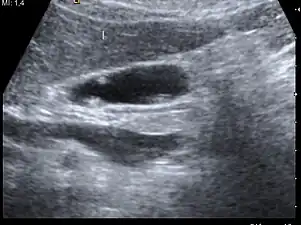

| A polyp in the gall bladder as seen on ultrasound |

Ultrasound image of gallbladder polyps measuring 3–7 mm.